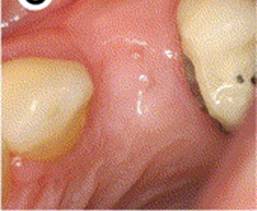

4 MONTH HEALING